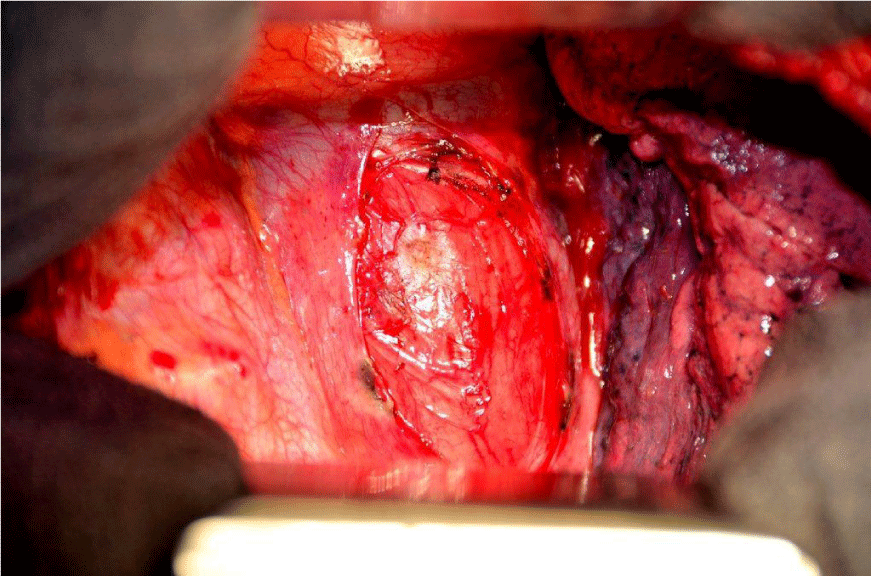

After repeated discussion of this patient in the interdisciplinary tumour board of the University Cancer Center (UCC), we performed an explorative right-sided dorsolateral thoracotomy in order to prove the malignant histology of this tumour and to relieve the patient of his symptoms. While technicaly feasible, a laryngo-pharyngo-esophagectomy as treatment with curative intent was not favoured by the patient. Intraoperatively, we discovered gross dilatation of the thoracic esophagus up to 8 cm in diameter caused by the intraluminal tumour mass (Figure 6). Via longitudinal esophagotomy, two large pedunculated tumours originating from the cervical esophagus and hypopharynx were protruded and (Figure 7) debulking of these intraluminal tumour masses was achieved with an Endo-GIA-Stapler device (Figure 8). The postoperative course was uneventful, and the patient was discharged from the hospital on day 13.

Figure 6: Right-sided thoracotomy: dilatation of the esophagus up to 8 cm in diameter due to intraluminal tumour mass.

Figure 7: Right-sided thoracotomy and esophagotomy: large pedunculated tumors originating with broad base in the cervical esophagus and hypopharynx protruding out of the esophageal lumen.